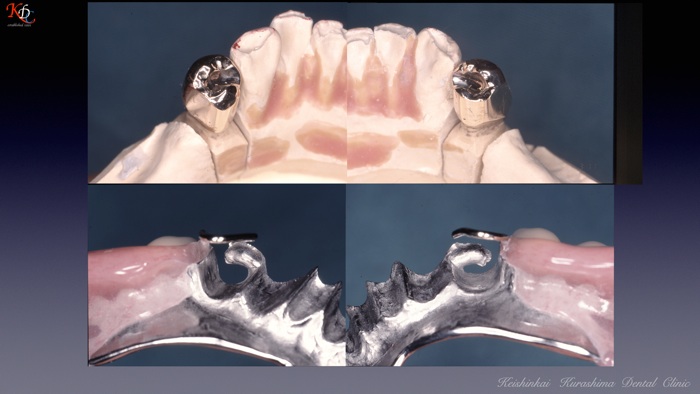

治 療例 1